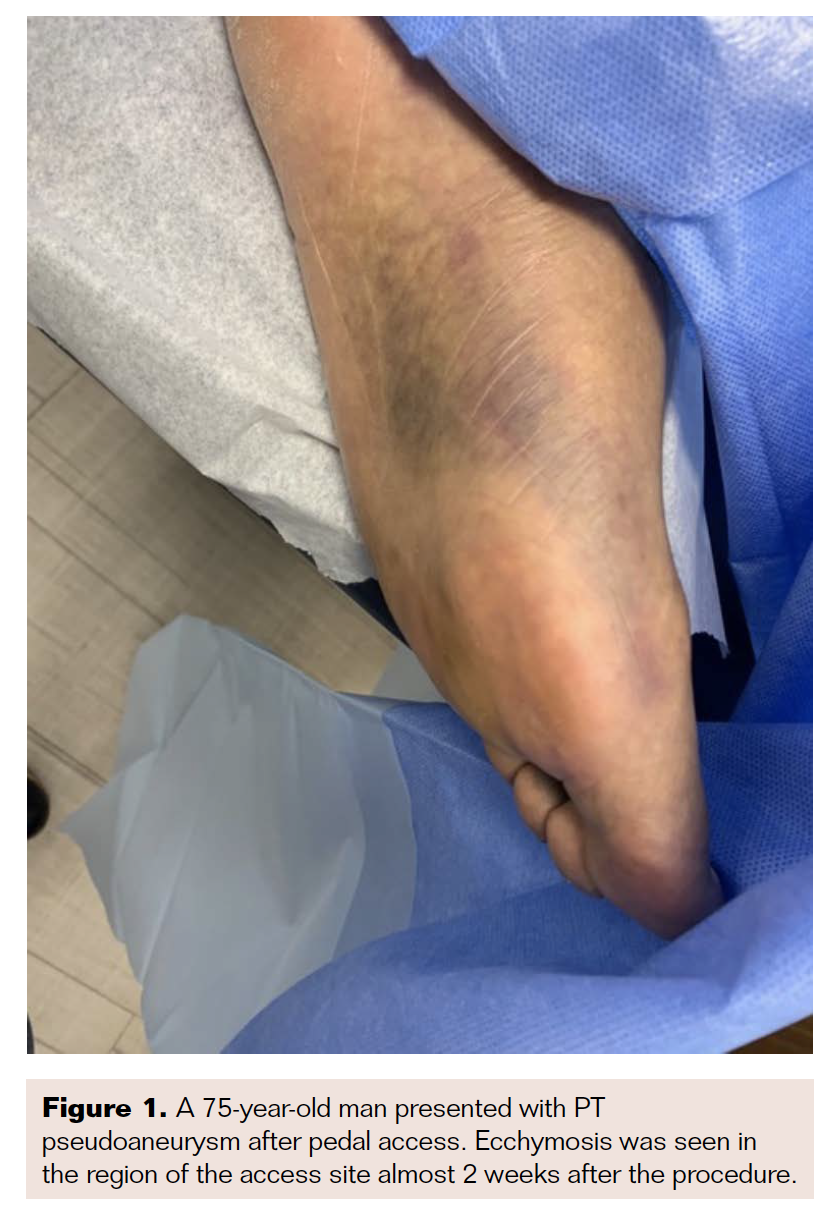

The patient was placed in the supine position for 4 hours after the procedure. Follow-up ultrasound scans at 5, 15, 30, 60, 120, and 240 minutes after the procedure showed good distal flow in the left posterior tibial artery, with stable thrombosis of the sac, after which the patient was discharged home. Forty-eight hours later, follow-up ultrasound demonstrated a widely patent PT artery with no flow in the pseudoaneurysm (Figure 5). At 3-month follow-up, there was complete resolution of pain, swelling, and bruising, and the PT showed good flow on color Doppler ultrasound (Figure 6).